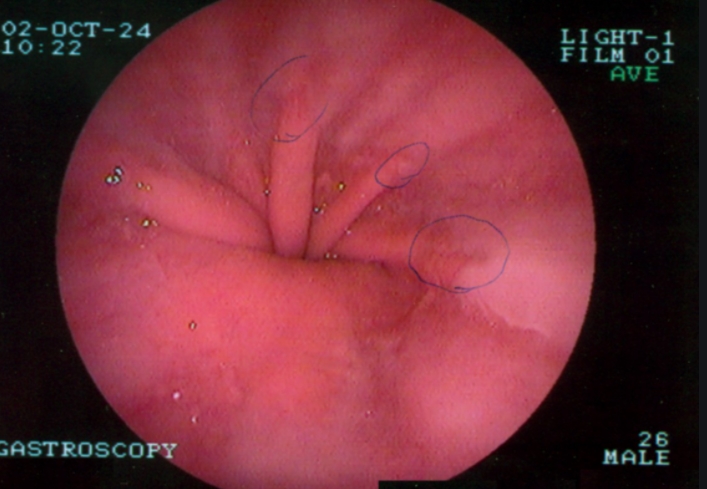

위내시경 받기 위해서는 다른 건 다 필요없습니다. 오로지 금식시간 잘 지켜 주시는 것 하나 입니다. 수면내시경 또는 일반내시경 중 선택해서 검사를 받으면 되는데요, 목구멍을 지나 식도와 위 그리고 십이지장 윗부분까지도 볼 수 있는 것이 바로 이 위내시경 입니다.

8시간 이상의 금식시간 그리고 여러 사전준비를 거쳐 검사에 들어가게 됩니다. 왼쪽으로 누워서 입으로 관을 삽입하게 되는데 이때 검사를 받는 사람의 입장에서 중요한 것은 트림을 참아야 한다는 점입니다.